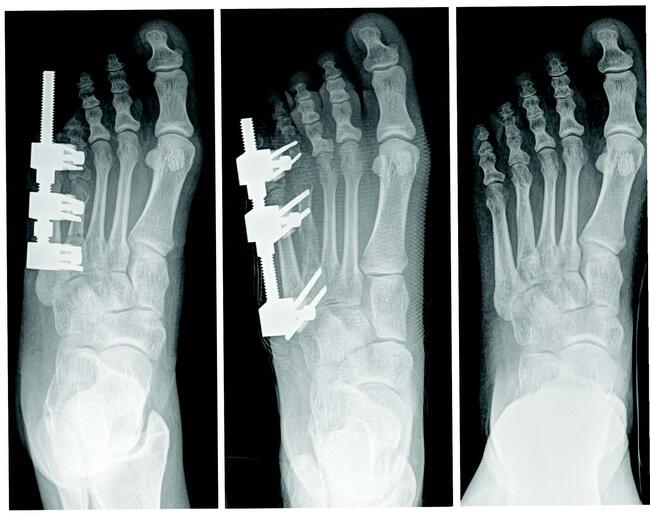

Tricortical radiographic consolidation on two orthogonal radiographs mark achievement of bony consolidation. Computed tomography may be necessary to confirm complete osseous healing in foot and ankle cases. Obtaining this endpoint then allows for removal of the external fixation.

Rate and rhythm in distraction osteogenesis significantly impacts the expression of factors involved.18 Further, several experimental studies show improved bone regeneration with continuous versus intermittent distraction osteogenesis.21 One begins distraction at a specific rate and rhythm, typically 1.0 mm a day, divided into four increments. Although this is the classically cited rate, in clinical practice, the rate can vary (0.5 mm/day to 1 mm/day in the foot and ankle) based on multiple factors including: patient age, health, medications, location and type of osteotomy.

Other reported complications include joint stiffness and subluxation, as well as osseous malalignment. During lengthening, there is a tendency for the bone segment in question to gradually veer off its intended course due to muscle forces or instability secondary to an inadequate external fixator construct.2,9,10 Other complications relate to the consolidation rate at the distraction site. Premature consolidation occurs as a direct result of an excessive latency period in which significant callus healing blocks the distraction. In contrast, prolonged or delayed consolidation can occur secondary to patient metabolic, environmental, or technical factors including: poor osteotomy technique, initial diastasis, or rapid distraction.9,10 Pin site tract infections, fracture after external fixator removal, and chronic regional pain syndrome have also been reported.19